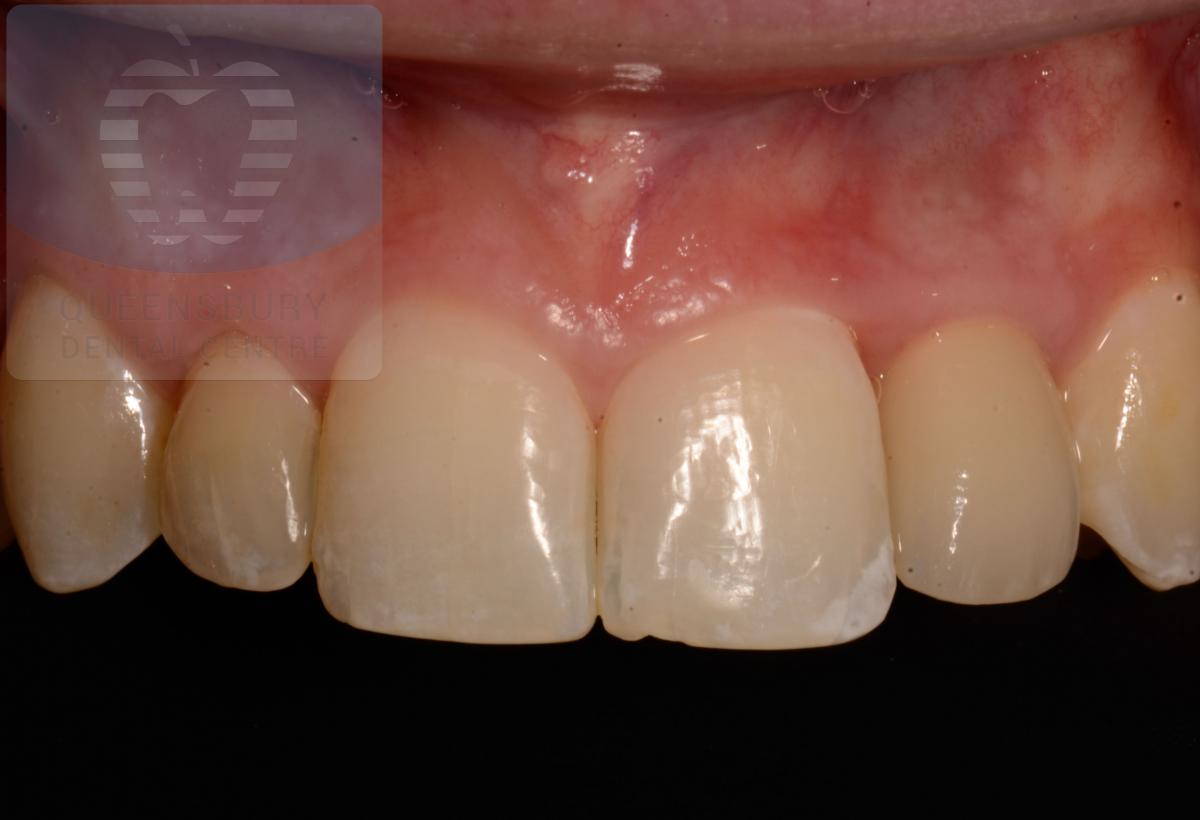

Missing teeth and loose dentures make many people avoid social settings because they are too self-conscious about their appearance. Current dental procedures, however, replace everything from a single missing tooth to a completely missing arch. Ask your dentist or dental specialist about the different dental options that are available to you. Don’t let another day go by without taking this important first step to restoring your confidence and your smile!